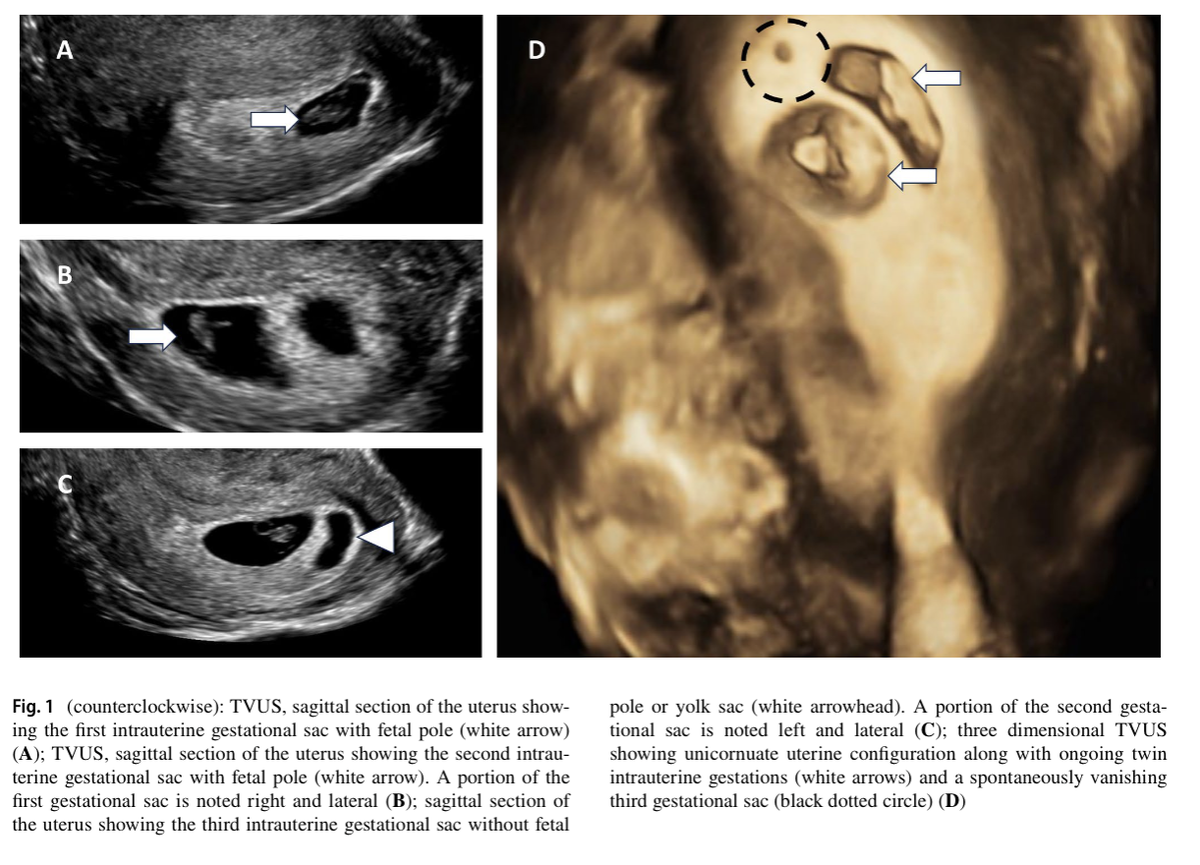

Рис. 1 (против часовой стрелки): ТВУЗИ, сагиттальный срез матки, показывающий первый внутриматочный плодный мешок с эмбриональным полюсом (белая стрелка)

(A); ТВУЗИ, сагиттальный срез матки, показывающий второй внутриматочный плодный мешок с эмбриональным полюсом (белая стрелка). Часть первого плодного мешка видна справа и сбоку

(B); сагиттальный срез матки, показывающий третий внутриматочный плодный мешок без эмбрионального полюса или желточного мешка (белая стрелка). Часть второго плодного мешка видна слева и сбоку

(C); трехмерное ТВУЗИ, показывающее конфигурацию однорогой матки вместе с развивающейся двойней внутриматочной беременности (белые стрелки) и самопроизвольно исчезающий третий плодный мешок (черный пунктирный круг) (D).